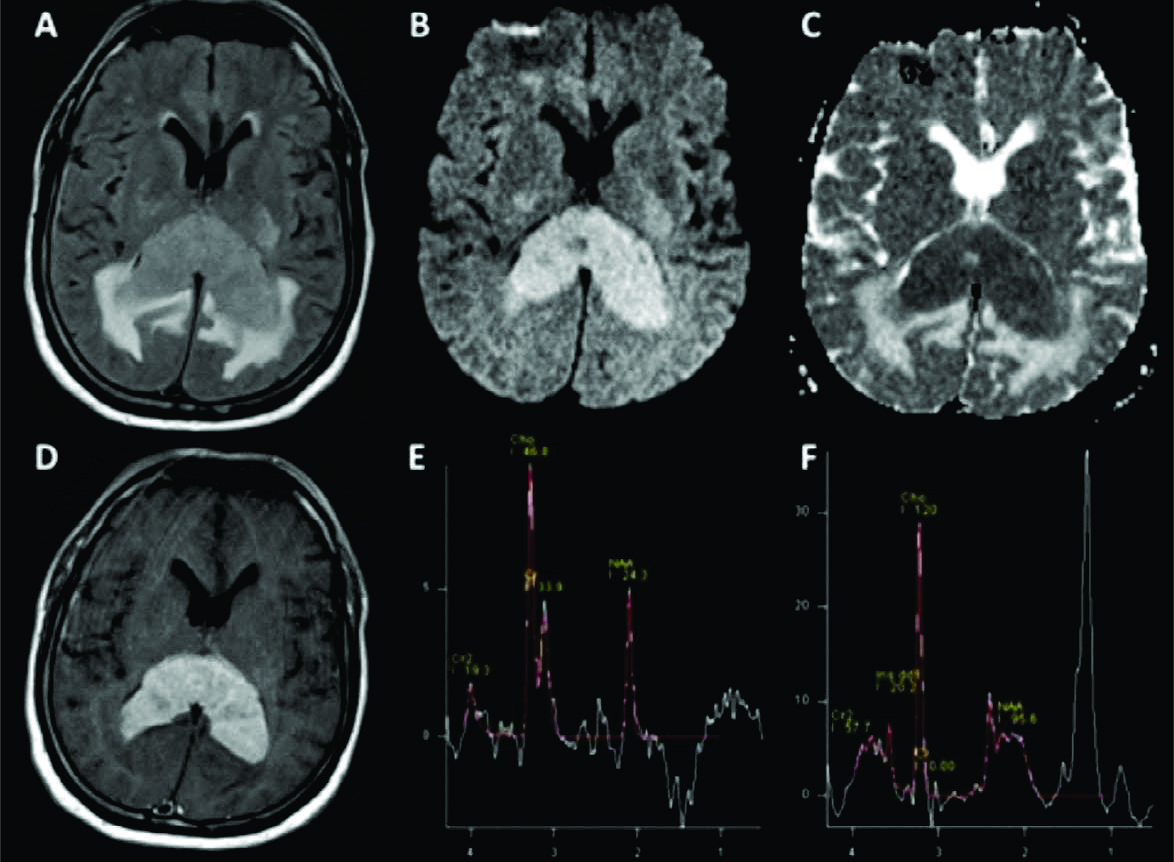

Figura 6

LPSN clásico con compromiso del CC, espectroscopía.

Pacientes con una típica lesión de CC hiperintensa en FLAIR (A) con edema, restricción en difusión (B) y ADC (C) e intenso realce homogéneo con el contraste (D). Los trazados metabólicos obtenidos muestran en eco largo (E) un ascenso de Ch con descenso de NAA que confirma la naturaleza tumoral de la lesión.

En el tiempo de eco corto (F) se mantiene este hallazgo y se hace evidente un significativo pico de Lip/Lac típico de estas lesiones, sin mioinositol.

Este patrón fue el obtenido en la mayoría de las lesiones de esta serie.

Los trazados metabólicos obtenidos mostraron en todos los casos un descenso de los niveles de NAA y ascenso de la Ch con ascenso de los niveles de Cr en 15 casos. No se observó niveles significativos de mI en ningún caso mientras que el pico de Lip/Lac estuvo presente en todas lesiones analizadas con elevación variable.

En relación con los índices o ratios metabólicos el Ch/NAA tuvo un valor promedio de 2,29 con un rango de 1,03 a 3,65; Ch/Cr de 2,08 con rango de 0,68 a 4,5; y NAA/Cr de 1,08 con un rango de 0,45 a 1,78. Figura 6 En todos los casos analizados fue sugerido el diagnóstico de LPSN apoyado sobre todo en la topografía de las lesiones, su comportamiento en secuencia T2, difusión y mapa de ADC y patrón de realce con el medio de contraste.

Este patrón tumoral fue el más frecuente en nuestra serie con aumento de Ch en todos los casos con índice Ch/Cr que a diferencia de los reportado estuvo en promedio por debajo de 3. Figura 6

En todos los casos de nuestra serie se observó pico de Lip/Lac.